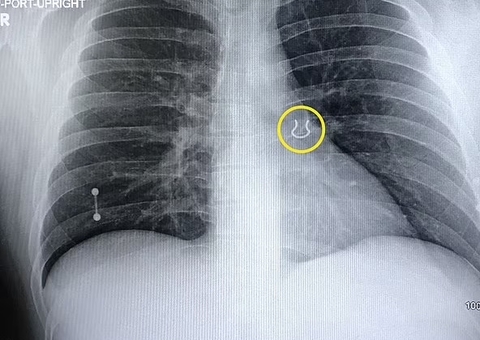

Após sentir fortes dores abdominais, o homem procurou o hospital e surpreendeu os médicos quando exames de raio-x revelaram a causa do mal-estar. O paciente ficou 20 dias sem conseguir fazer cocô e os médicos informaram que ele corria risco de morte.